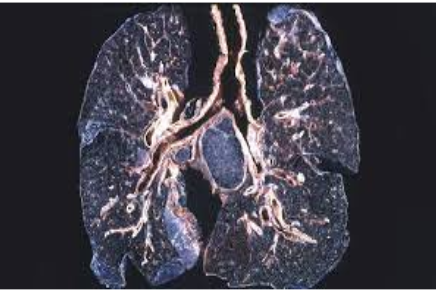

Q1. An industrial worker reported with cough, dyspnoea on exertion, and chest pain. His Chest X-ray showed a "snow storm appearance." What is the diagnosis? (1)

Diagnosis: Silicosis (A chronic fibrotic lung disease caused by the inhalation of crystalline silica dust).